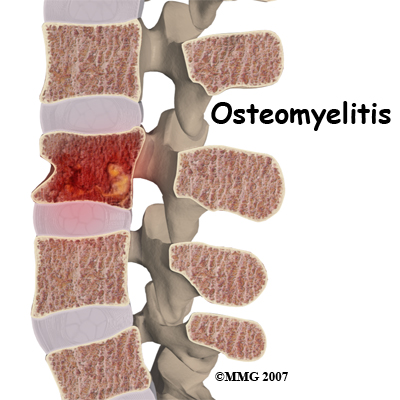

Discitis and vertebral osteomyelitis are rare in children. When a disc becomes inflamed and possibly infected, the condition is called discitis. If the vertebral bone becomes infected, the condition is called vertebral osteomyelitis.

Common symptoms of these conditions include refusal to crawl, sit, or walk and complaints of back pain. A limp and forward bending while placing the hands on the thighs for support are also common signs.

With discitis, the disc will appear narrowed on an X-ray or an MRI. Discitis usually occurs in children less than five years old.

Vertebral osteomyelitis tends to affect older children and adolescents. The vertebral bone and surrounding tissue including the disc can become infected. On X-ray or MRI the bone and/or tissue can show destruction. Fever of 102 degrees Fahrenheit or 39 degrees Celsius or greater is common in vertebral osteomyelitis.

Both discitis and vertebral osteomyelitis are treated with rest, as well as oral and IV antibiotics. A brace to support the spine may be suggested. With osteomyelitis surgery may be necessary to clean out the infection and/or to stabilize the spine.